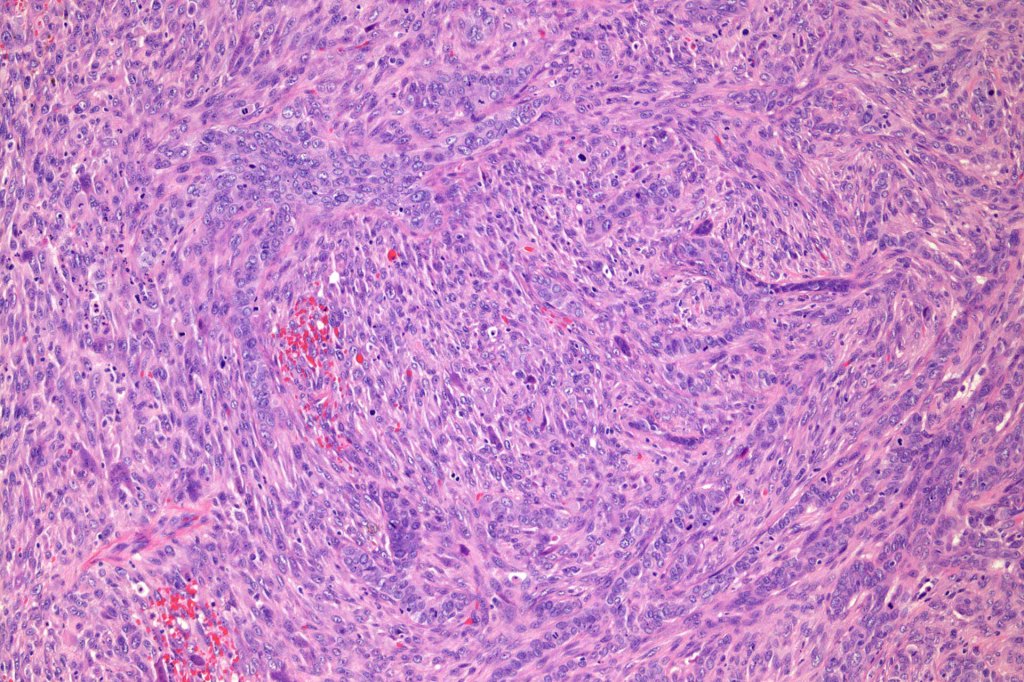

Carcinosarcoma

Cutaneous carcinosarcoma (metaplastic carcinoma, carcinoma with heterologous differentiation)

Histological features

•Osteoid

•Chondroid

•Smooth muscle

•MFH-like features with osteoclasts

•Neural differentiation